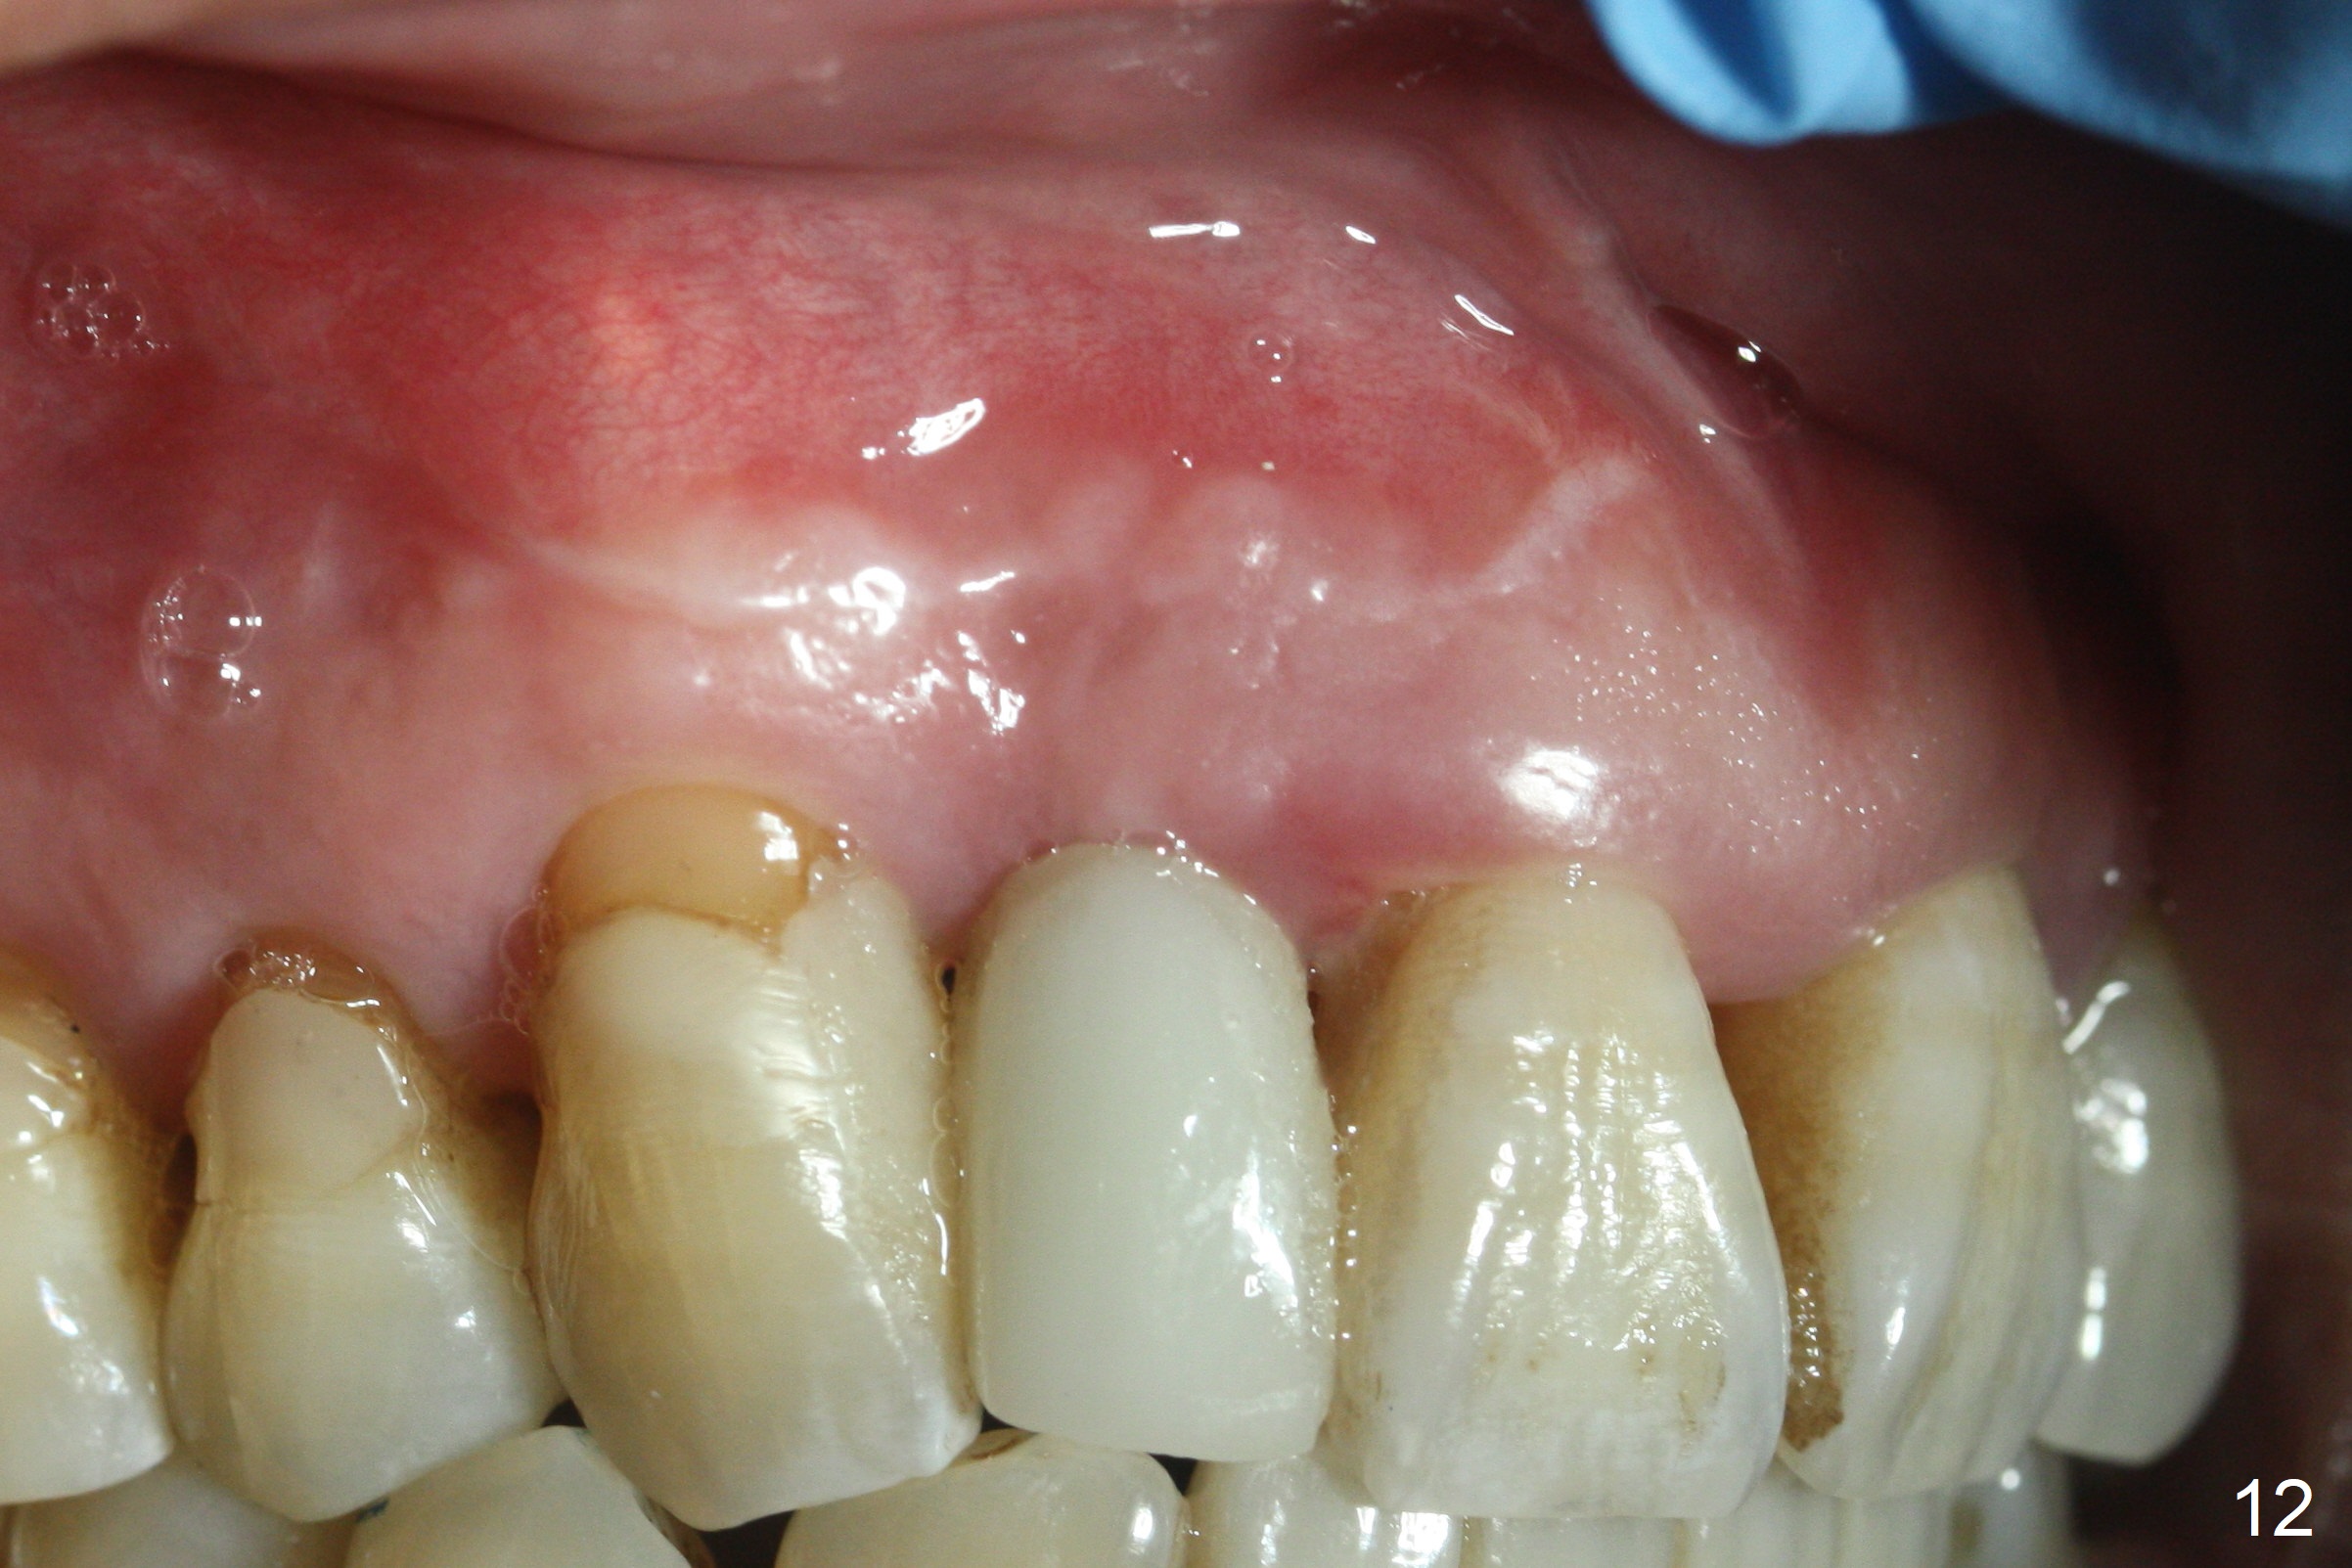

Extending the initial osteotomy to the full length of the implant is critical. If perforation is detected early, the trajectory can be changed. Incision should be made if there is no CBCT study. The incision heals 1 and 4 weeks postop (Fig.8,9). The patient returns for final restoration 6 months postop. Apical defects appear to have healed at #6 and 7 (Fig.10,11). Fig.12 is taken 11 months postop and 5 months post cementation. The patient has an accident 9 months post cementation. In fact the implant is alright, while the tooth #6 fractures and #8 subluxates.